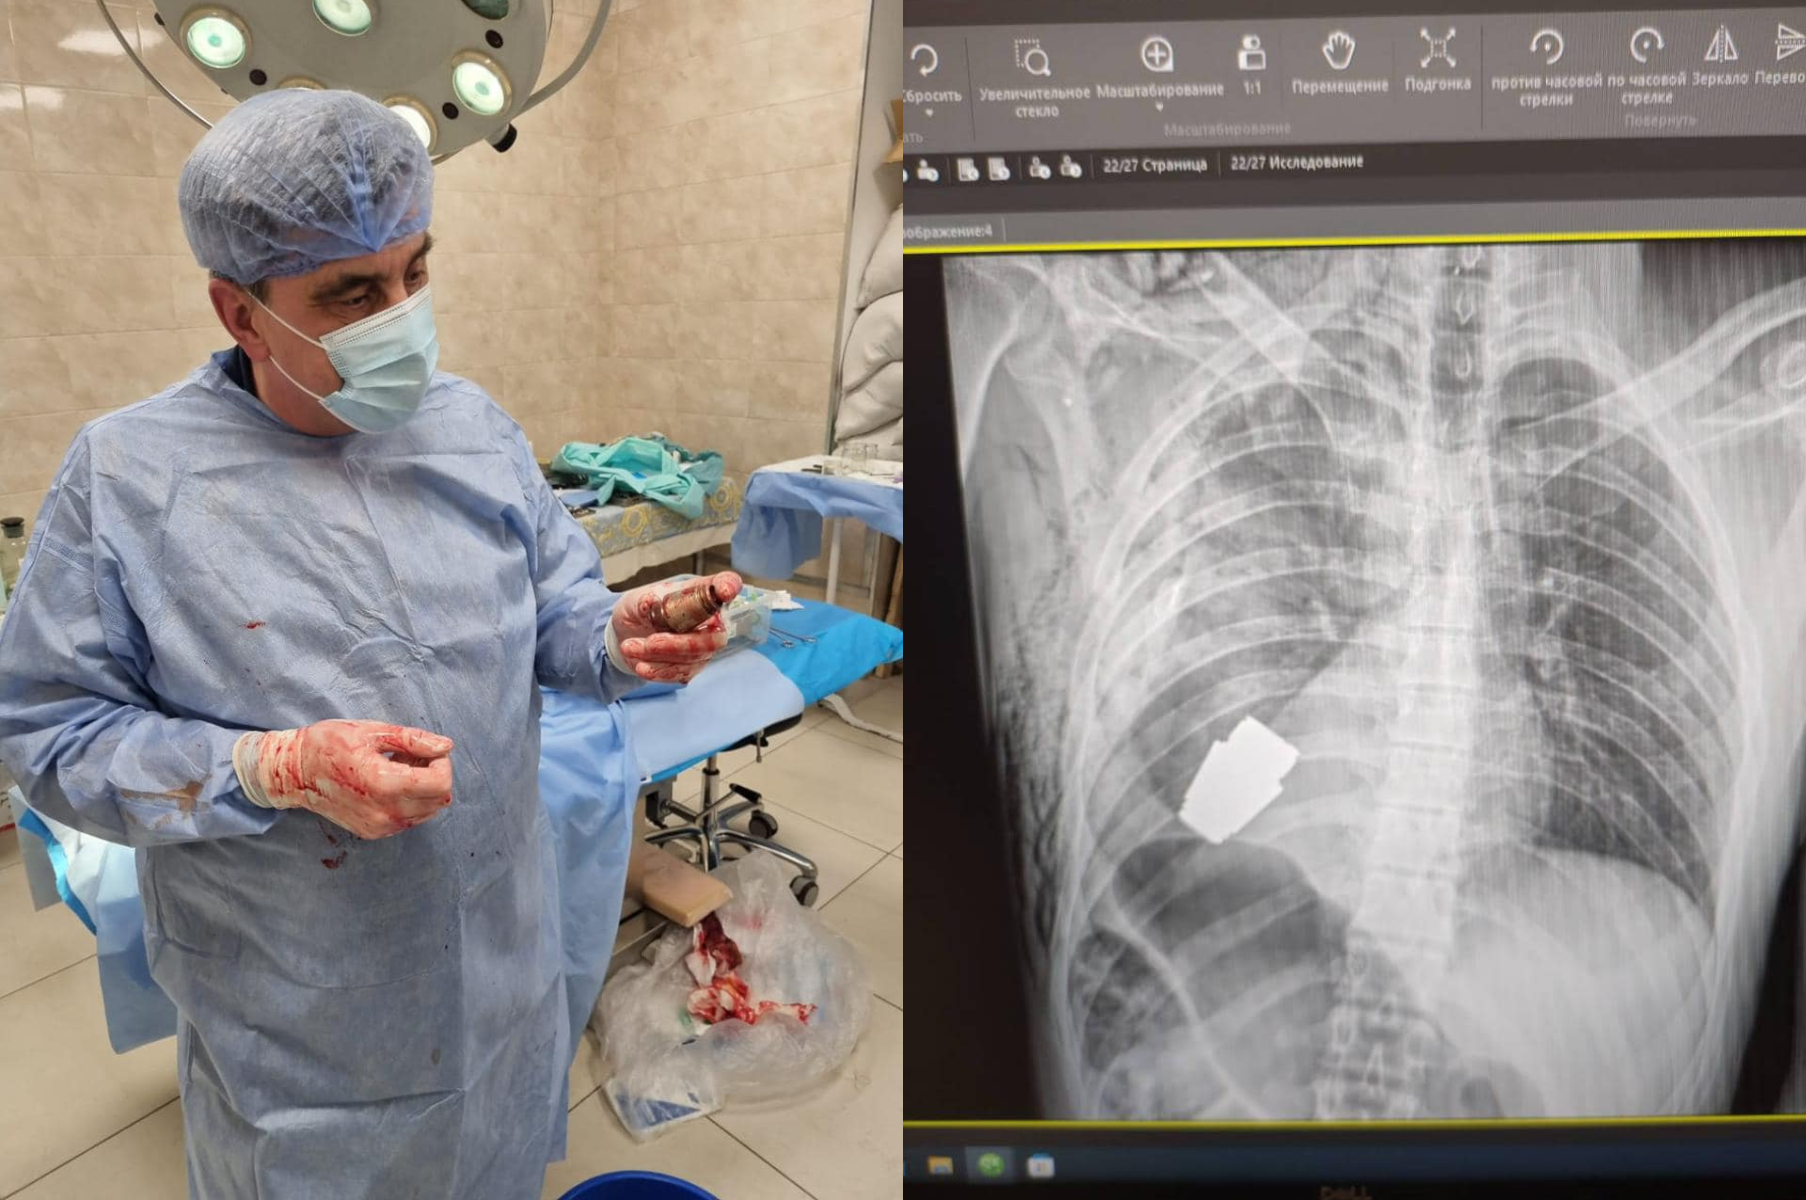

Kirurzi su uklonili eksplozivnu napravu točno ispod srca ozlijeđenog vojnika, a dva vojnika pobrinula su se da operacija bude sigurno izvedena, rekla je Hanna Maliar, zamjenica ukrajinskog ministra obrane. Ona je objavila i fotografiju na kojoj se vidi rendgenska snimka granate u vojnikovu tijelu.

“Vojni liječnici izveli su operaciju vađenja neraspadnute granate VOG iz tijela vojnika”, napisala je u objavi na Facebooku.

Operacija je izvedena bez upotrebe elektrokoagulacije - uobičajene metode za kontrolu krvarenja tijekom operacije - jer bi se tako granata mogla detonirati u bilo kojem trenutku, navela je Maliar.

Jedna slika prikazuje kirurga koji drži eksploziv nakon operacije.